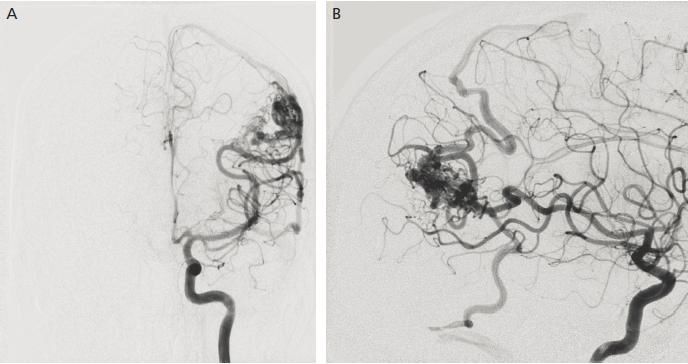

Removal of a tangle of pathological vessels to prevent intracranial hemorrhages.

Microsurgical removal of arteriovenous malformations is performed under general anesthesia using an operating microscope. After trepanation of the appropriate area, staged resection, electrocoagulation and clipping of all pathological vessels and removal of the malformation are performed.

After surgery (usually the next day), a computed tomography scan of the brain and cerebral angiography are performed.